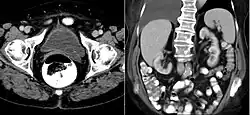

A ureterocele is a congenital abnormality found in the ureter. In this condition the distal ureter balloons at its opening into the bladder, forming a sac-like pouch. It is most often associated with a duplicated collection system, where two ureters drain their respective kidney instead of one. Simple ureterocele, where the condition involves only a single ureter, represents only twenty percent of cases.

IVU-shows Adder head appearance or Cobra head appearance. Cystoscopy-shows translucent cyst which is thin walled surrounding ureteric orifice